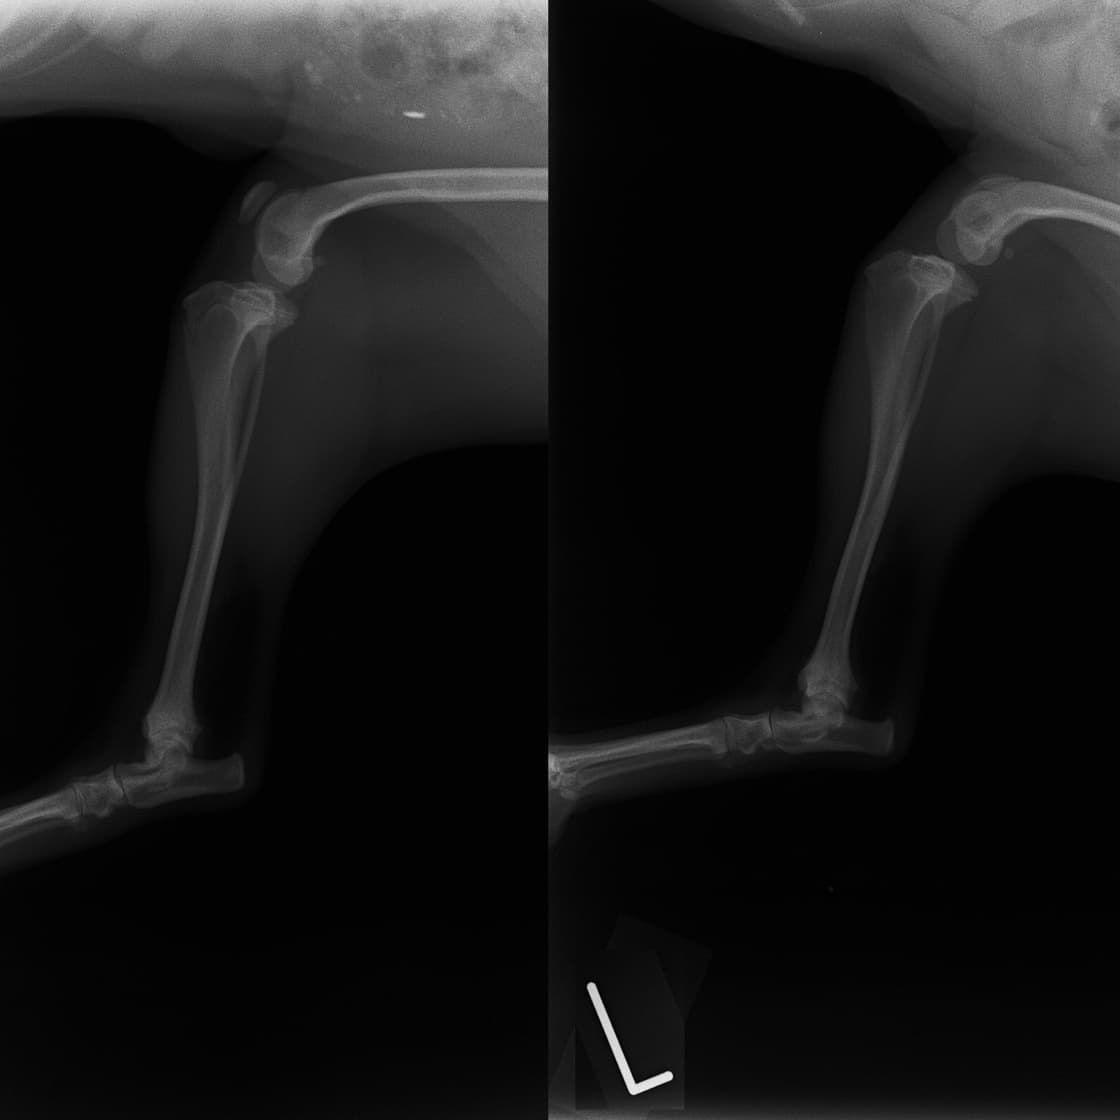

■ 症例22 ポメラニアン 1歳5か月 去勢雄

左後肢の挙上を主訴に来院した。整形学的検査、レントゲン検査より左右の膝蓋骨脱臼(左GradeⅡ〜Ⅲ、右Grade Ⅱ)を認めた。また、脛骨の前方引き出し試験の際に、引き出し兆候は認められないものの、疼痛が認められたため、前十字靭帯の損傷が疑われた。術中における、目視および関節内の操作によって、前十字靭帯の損傷や過伸展といった異常が認められなかったため、膝蓋骨脱臼の整復のみ実施した。手術手技は縫工筋及び内側広筋の解放、脛骨粗面の外側転位、滑車ブロック形造溝術、内外側関節包の縫縮を実施した。本症例は跛行もなく経過良好である。しかし、頸骨高平部の角度(TPA)が 右26.2°、左24.9°であり、解剖学的に前十字靭帯損傷のリスクが高いことから今後の経過に注意が必要である。